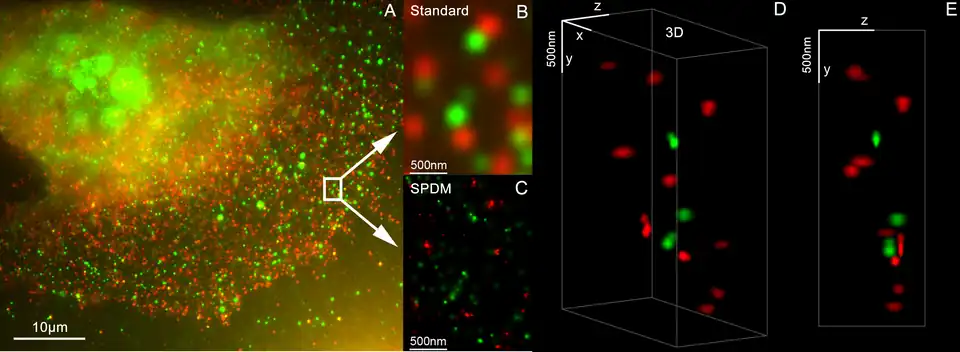

HER2 proteins have been shown to form clusters in cell membranes that may play a role in tumorigenesis.[26][27]

- ^ Kaufmann R, Müller P, Hildenbrand G, Hausmann M, Cremer C (April 2011). "Analysis of Her2/neu membrane protein clusters in different types of breast cancer cells using localization microscopy". Journal of Microscopy. 242 (1): 46–54. doi:10.1111/j.1365-2818.2010.03436.x. PMID 21118230. S2CID 2119158.